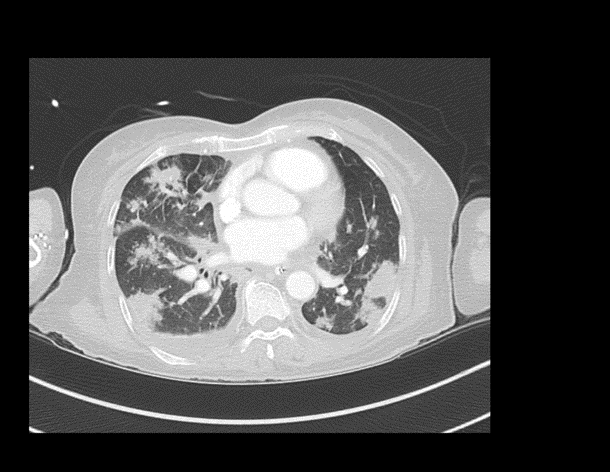

CASE 5 –A 57-year-old woman presented to the emergency department with fevers, cough and night sweats and recent weight loss. She arrived in Australia from Philippines 5 days previously. In the ED she had significant respiratory distress requiring high flow oxygen and subsequent intubation and ventilation as her respiratory failure progressed.

EXPLANATION -There is diffuse bilateral consolidation more prominent in the upper lobes.

There is left upper lobe cavitation. Bilaterally there are pleural effusions.